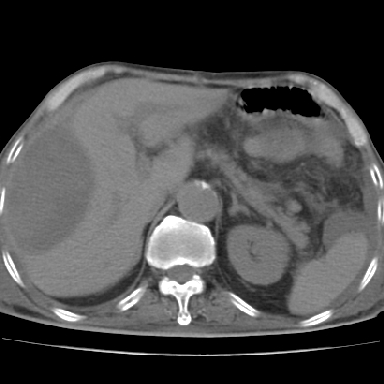

以下是引用qian在2006-12-4 19:11:00的发言:[br]胸腔和腹腔内均见有液性影,肝上极包膜下有一较大椭圆形低密度影,密度均匀,边缘清晰,结合病史考虑术后肝脓肿并胸腹腔积液。

以下是引用dyqct在2006-12-4 19:54:00的发言:[br]考虑:1、肝包膜下脓肿;[br] 2、少量腹水;[br] 3、右侧少量胸膜腔积液。